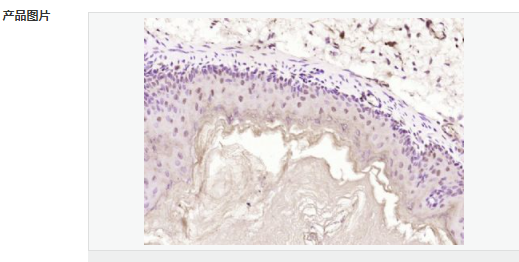

| 產品應用 | WB=1:500-2000 ELISA=1:5000-10000 IHC-P=1:100-500 IHC-F=1:100-500 ICC=1:100-500 IF=1:100-500 (石蠟切片需做抗原修復) not yet tested in other applications. optimal dilutions/concentrations should be determined by the end user. |

| 產品介紹 | Machado-Joseph disease, also known as spinocerebellar ataxia-3, is an autosomal dominant neurologic disorder. The protein encoded by this gene contains (CAG)n repeats in the coding region, and the expansion of these repeats from the normal 13-36 to 68-79 is one cause of Machado-Joseph disease. There is a negative correlation between the age of onset and CAG repeat numbers. Alternatively spliced transcript variants encoding different isoforms have been described for this gene. [provided by RefSeq, Sep 2009] Function: Interacts with key regulators (CBP, p300 and PCAF) of transcription and represses transcription. Acts as a histone-binding protein that regulates transcription. Acts as a deubiquitinating enzyme. Subcellular Location: Nucleus matrix. Predominantly nuclear, but not exclusively, inner nuclear matrix. Tissue Specificity: Ubiquitous. DISEASE: Defects in ATXN3 are the cause of spinocerebellar ataxia type 3 (SCA3) [MIM:109150]; also known as Machado-Joseph disease (MJD). Spinocerebellar ataxia is a clinically and genetically heterogeneous group of cerebellar disorders. Patients show progressive incoordination of gait and often poor coordination of hands, speech and eye movements, due to degeneration of the cerebellum with variable involvement of the brainstem and spinal cord. SCA3 belongs to the autosomal dominant cerebellar ataxias type I (ADCA I) which are characterized by cerebellar ataxia in combination with additional clinical features like optic atrophy, ophthalmoplegia, bulbar and extrapyramidal signs, peripheral neuropathy and dementia. The molecular defect in SCA3 is the a CAG repeat expansion in ATXN3 coding region. Longer expansions result in earlier onset and more severe clinical manifestations of the disease. Similarity: Contains 1 Josephin domain. Contains 3 UIM (ubiquitin-interacting motif) repeats. SWISS: P54252 Gene ID: 4287 Database links: Entrez Gene: 4287 Human Entrez Gene: 110616 Mouse Omim: 607047 Human SwissProt: P54252 Human SwissProt: Q9CVD2 Mouse Unigene: 532632 Human Unigene: 271914 Mouse Unigene: 42932 Rat Important Note: This product as supplied is intended for research use only, not for use in human, therapeutic or diagnostic applications. |